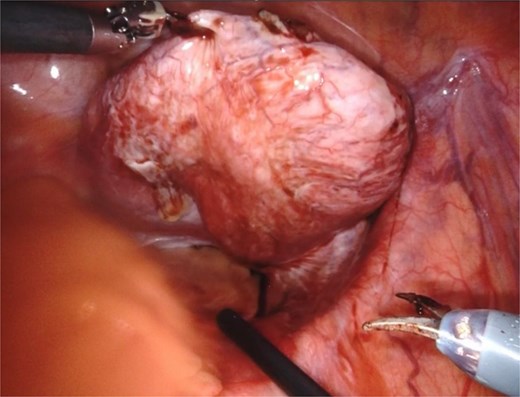

Based on the patient’s symptoms and imaging findings, robotic-assisted laparoscopic excision of the right seminal vesicle cyst was planned. The procedure was performed under general anesthesia using a da Vinci surgical system with a four-port approach. The patient was positioned in steep Trendelenburg position. A large right seminal vesicle cyst was identified posterior to the bladder (Fig. 2). Meticulous dissection was performed to separate the cyst from surrounding structures. The cyst contents were aspirated, yielding 150 cc of brownish fluid (Fig. 3). Complete excision was achieved while preserving the bladder neck, left ureter, and neurovascular bundles. Hem-o-lok clips were applied to secure the base of the cyst. Complete hemostasis was achieved, and there were no intraoperative complications.

An intraoperative image showing a large right seminal vesicle cyst identified posterior to the bladder.

The seminal vesicle cyst after dissection of surrounding tissue and fluid aspiration (150 cc).